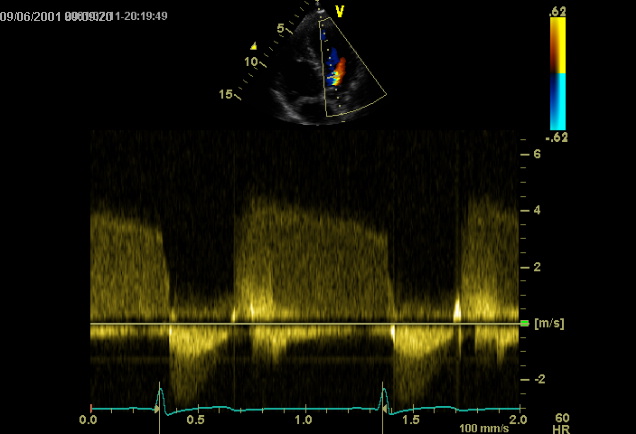

IAo

Aspect d'insuffisance aortique peu sévère (temps de demi-décroissance prolongé)

...en mode Doppler pulsé et continu: l'apicale 5 cavités est la fenêtre ultrasonore de prédilection pour explorer la voie d'éjection du VG. En plaçant, en mode Doppler pulsé le volume de mesure sous les sigmoïdes aortiques dans la chambre de chasse du VG, on enregistre en systole un flux négatif dont la vélocité est de l'ordre de 1m/s chez l'adulte. Le Doppler continu mesure les vélocités du flux transaortique. L'enregistrement simultané des clics des valves sigmoïdes permet de distinguer en systole les flux orificiels aortiques des flux de la voie d'éjection du VG